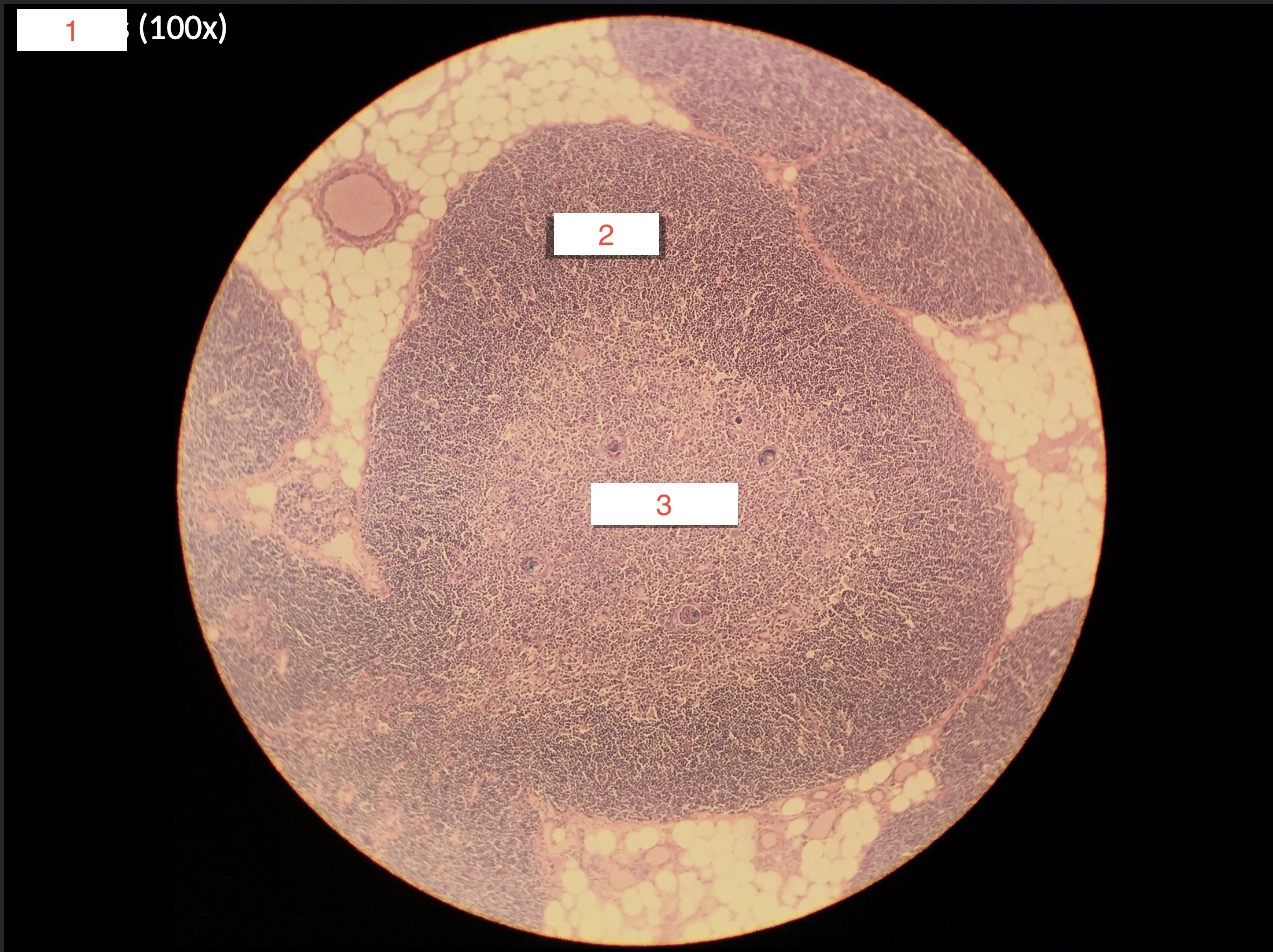

1- What is this slide?

Spleen

2

Artery

3

Red pulp

4

White pulp